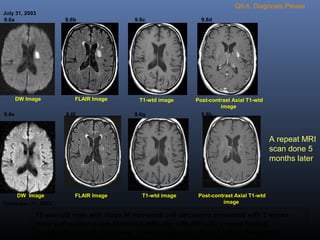

Q9.6. Diagnosis Please

July 31, 2003

T1-wtd imageDW Image FLAIR Image Post-contrast Axial T1-wtd

image

9.6a 9.6b 9.6c 9.6d

December 31, 2003

DW Image FLAIR Image T1-wtd image Post-contrast Axial T1-wtd

9.6e 9.6f 9.6g 9.6h

73 year-old male with stage IV non-small cell carcinoma presented with 2 weeks

history of sudden onset of speech difficulty with difficulty in word finding,

symptoms gradually improved. Clinical diagnosis: Stroke versus metastasis.

A repeat MRI

scan done 5

months later

Diagnosis: Non-hemorrhagic subacute enhancing infarct (2 weeks old)

involving the left basal ganglia region. Subacute infarct is seen as an area

of increased signal intensity on FLAIR image (arrow in B) and bright signal

intensity on DWI (arrow in A). Enhancement of the infarct is shown on post

contrast image (arrow in D).

A repeat MRI scan done 5 months

later showed resolution of infarct and

no evidence of bright signal intensity

on diffusion weighted image E.

5 months old infarct.